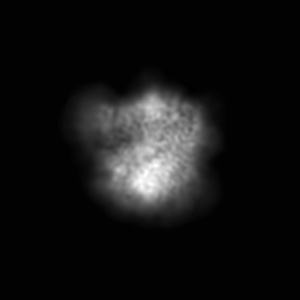

Cryo-EM map of DH898.1 Fab-dimer bound near the CD4 binding site of HIV-1 Env CH848 SOSIP trimer

Single-particle4.7 Å

Sample: Cryo-EM structure of DH898.1 Fab-dimer bound near the CD4 binding site of HIV-1 Env CH848 SOSIP trimer.